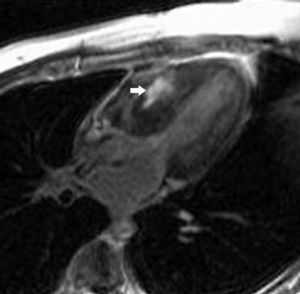

ABSTRACT: Breast metastasis from extramammary malignancy is rare, with a reported incidence rate of 0.4% to 1.3% in the published literature. The primary malignancies that most commonly metastasize to the breast are leukemia, lymphoma, and malignant melanoma. Here, we report a very rare case of metastatic EGFR-mutated non–small cell lung cancer (NSCLC) in the breast detected by screening mammography. The patient had initially been diagnosed with a clinical stage IIIA NSCLC and had been treated with neoadjuvant chemoradiation followed by curative-intent surgery. Several interesting aspects of the case, along with a discussion of evolving adjuvant and frontline metastatic management options in EGFR-mutated NSCLC, will be presented.